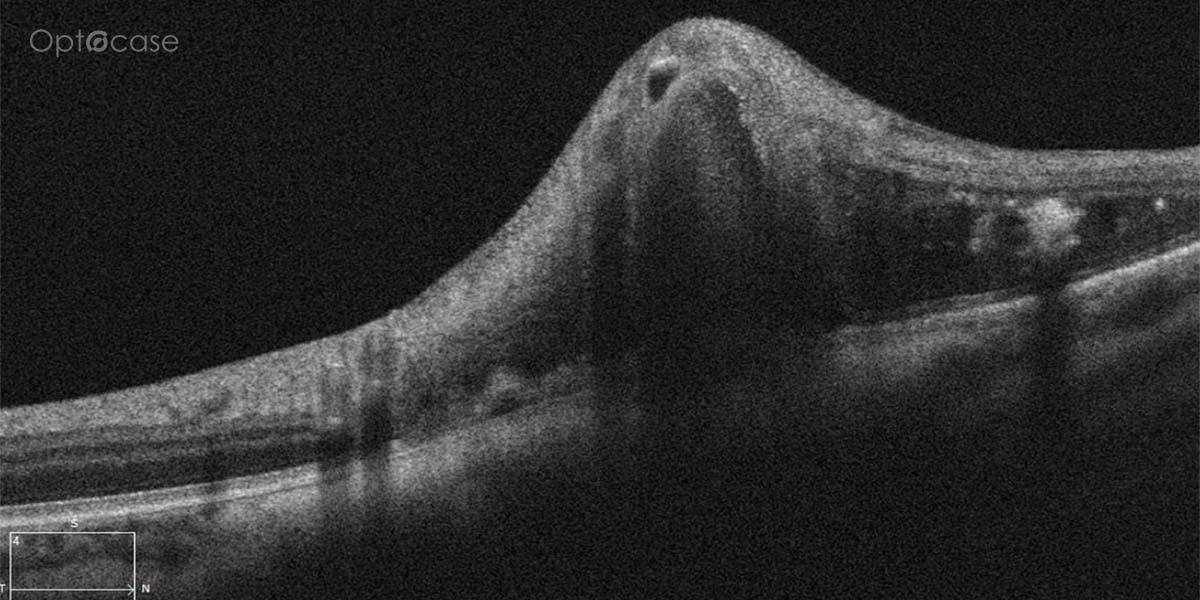

Here there is loss of the regular macular depression. There is a bright line present on the surface of the retina. In addition, there is separation of the retinal layers in the inner retina.

The patient was diagnosed with a schisis secondary to an epiretinal membrane. This complication is seen in over 50% of ERMs (video).